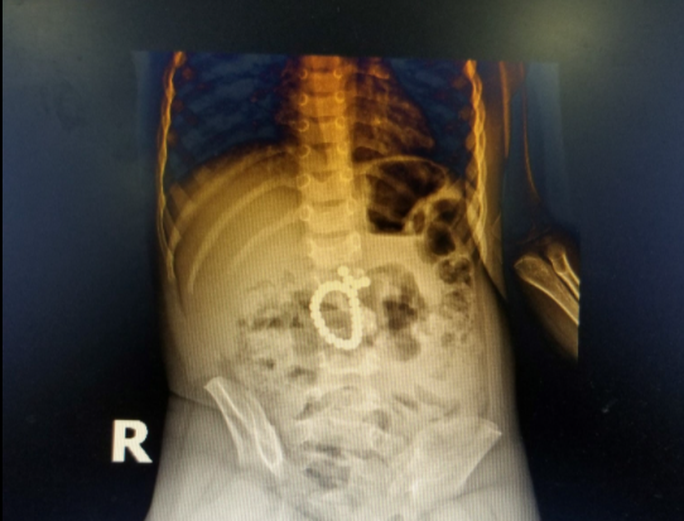

07/01/2022 00:19Nuốt 25 viên bi nam châm đồ chơi, bé trai hơn 3 tuổi bị thủng ruột

Ngày 6-1, Bệnh viện Sản Nhi Nghệ An cho biết vừa phẫu thuật cấp cứu thành công bệnh nhi 37 tháng tuổi (trú TP Vinh) do nuốt phải 25 viên bi nam châm đồ chơi vào ổ bụng.

Trước đó, chiều 5-1, bé T. được chuyển từ bệnh viện tuyến dưới đến Bệnh viện Sản nhi Nghệ An trong tình trạng đau bụng dữ dội.

Từ kết quả xét nghiệm và phim chụp X-quang ổ bụng, bác sĩ phát hiện bệnh nhân bị tắc ruột do dị vật hình tròn, gồm nhiều viên nhỏ dính thành chuỗi trong ổ bụng nên quyết định mổ cấp cứu.

Sau 3 giờ liên tục, các bác sĩ đã gắp 25 viên bi ra khỏi bụng bé T., đồng thời tiến hành khâu kín vị trí ruột thủng.

Tuy nhiên, trường hợp trẻ nuốt phải chuỗi bi nam châm đồ chơi như trên là cực kỳ nguy hiểm. Vì khi vào bụng, các viên bi nam châm sẽ có xu hướng tự hút dính vào nhau, gây tắc và tạo sức ép lên thành ruột dẫn đến thiếu máu cục bộ, từ đó dẫn tới hoại tử và thủng ruột, gây sốc nhiễm trùng, dẫn tới tử vong.